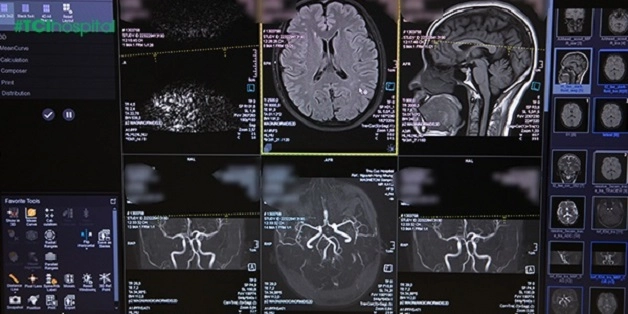

4. Chụp cộng hưởng từ (MRI) phương pháp chẩn đoán hình ảnh hệ thần kinh ưu việt

Có thể nói chụp cộng hưởng từ (chụp MRI) ra đời là một bước tiến vượt bậc trong lĩnh vực chẩn đoán hình ảnh. Phương pháp này cắt lớp phức tạp hơn chụp cắt lớp vi tính MSCT. Chụp MRI có thể cắt nhiều mặt, tái tạo hình ảnh 3D, phân tích được các tổn thương trong mô mềm, thần kinh não, tủy rất lý tưởng.

Đặc biệt là chẩn đoán bệnh lý về mạch máu não và tủy sống, không cần tiêm thuốc đối quang từ vẫn cho hình ảnh rõ nét, độ chính xác cao. Thuốc đối quang được sử dụng tùy thuộc vào từng trường hợp cụ thể do bác sĩ chẩn đoán hình ảnh quyết định.

So với chụp cắt lớp vi tính thì chụp cộng hưởng từ MRI có độ nhạy và đăc hiệu cao hơn, nên được ứng dụng rộng rãi trong chẩn đoán bệnh lý về thần kinh và rất nhiều bệnh lý ở các cơ quan khác trong cơ thể. Có thể dùng để kết hợp với các phương pháp chẩn đoán hình ảnh khác.

Đây là phương pháp khảo sát sọ não, mạch máu não an toàn (có thể áp dụng ở cả người cao tuổi, trẻ em, phụ nữ đang mang thai), không xâm lấn, cho hình ảnh rõ nét, đánh giá kỹ tổn thương, phát hiện bất thường nhỏ nhất để có biện pháp can thiệp và điều trị kịp thời.

Chụp cộng hưởng từ MRI là phương pháp chẩn đoán hình ảnh ưu việt nhất hiện nay đặc biệt là khảo sát các vấn đề về não, tủy sống.